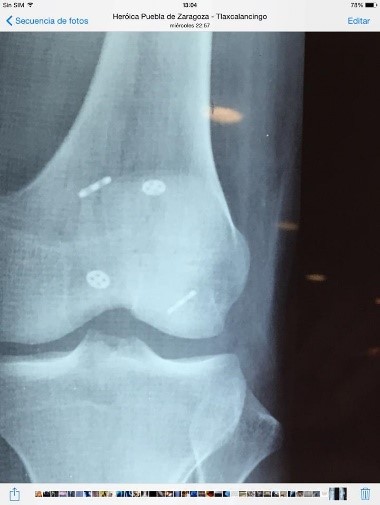

Dr. Jose Mario Dorantes Rodríguez, Ortopedista y Traumatólogo

• Casos clínicos